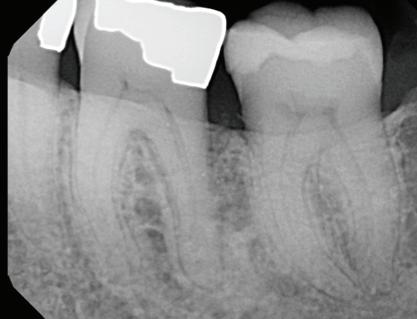

year old female patient presented with clinical and radiographic evidence of an mm.

year old female patient presented with clinical and radiographic evidence of an mm

-year follow-up radiographs showed evidence of bone fill. Clinically, maturation of interdental tissue is evident as well

Stability of the bone radiographically is evident as well.

-year follow up clinical photos are demonstrating stability of bone, lack of facial and minimal interproximal recession. Stability of the bone radiographically is evident as well.

-year follow-up radiographs showed evidence of bone fill. Clinically, maturation of interdental tissue is evident as well.